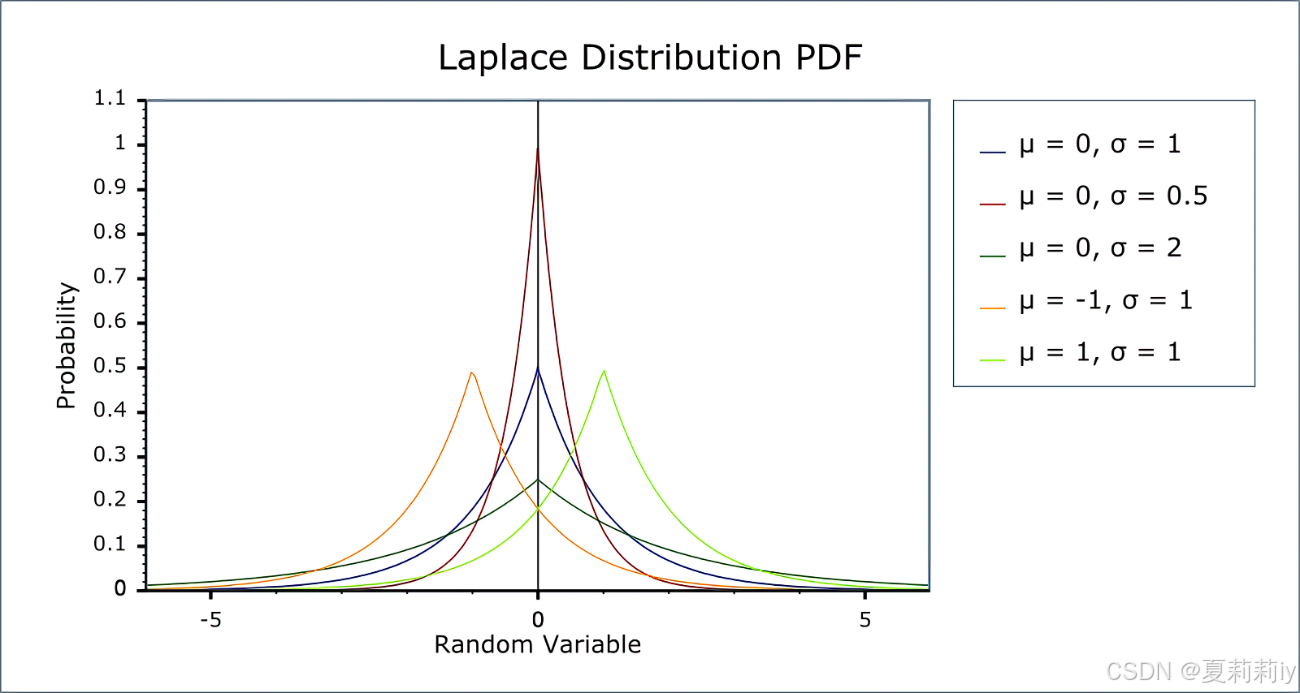

⑤Laplace Mechanism: 我先随便插几张拉普拉斯分布的图,可以见得它和高斯分布有点类似只是是尖尖的,而且也是俩参数,公式还比高斯看起来简单一点:

They employ Laplace Distribution with scale :

and , the

noise will be add to

, the difference privacy is

(作者只用了一个参数咩~)。然后他们为了简化讨论假定灵敏度

为1???这能假定吗?这不是两个数据集间的差异吗。我猜测作者是在说两个站点间参数的差异为1?